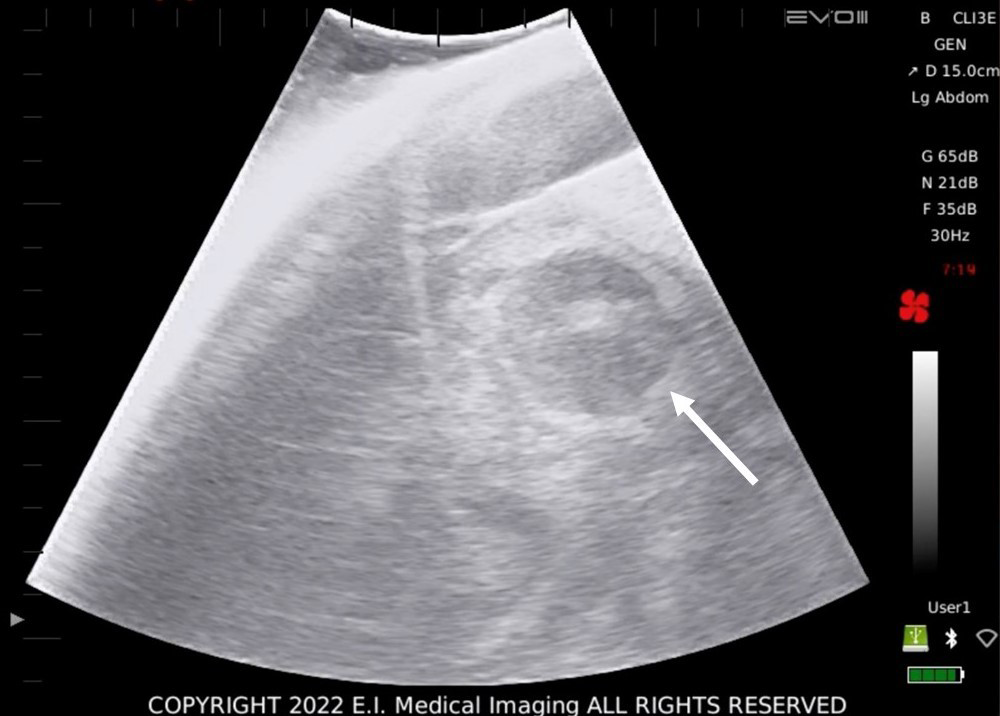

Over the course of the two 20 minute dives, individual sharks made several passes and based on the analysis of the Aquanaut video, three sharks were identified to be gravid (Figure 4) by the presence of identifiable embryos within the uterus (Sulikowski and Hammerschlag, 2023). Proprietary software measurements from still images indicated the embryos measured were approximately 4 cm in circumference. While the exact location and orientation of the embryos could not be determined, given the short duration of transducer shark contact, the observed sizes are similar to those reported from a gravid female captured on November 22nd-2022 by local fishermen in Isla Mujeres, Quintana Roo (a nearby location to Playa del Carmen), during a fishing survey realized by Save Our Sharks staff.

Figure 4

Representative transverse ultrasound images of bull shark Carcharhinus leucas obtained from gravid females with identified embryos in utero. Arrows point to the embryo.